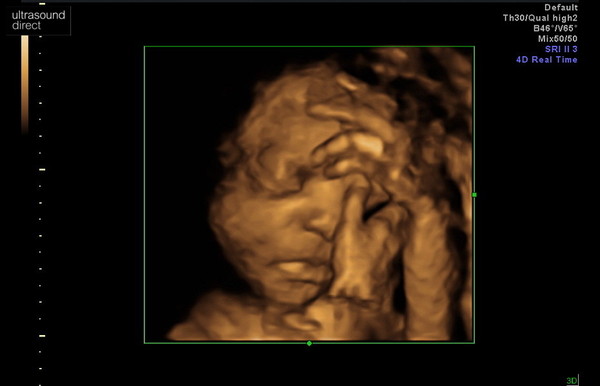

On a more positive note, I went for a private growth scan last Tuesday and got to see my little bubba in 4d. She was sleeping in the cutest position ever.

@Asianchick6693 - that is so cute!!

@Asianchick6693 lovely scan photo and congratulations on getting to 28 weeks.